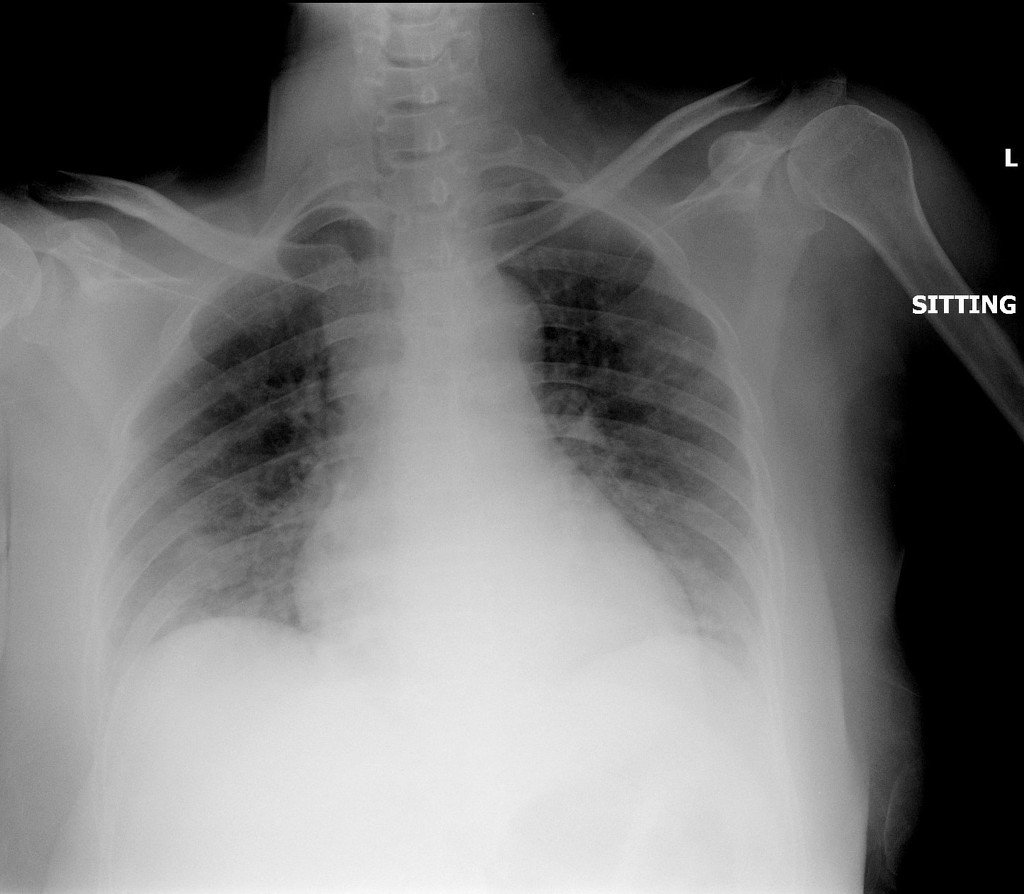

Chest Imaging in COVID-19 patient management is becoming an essential tool for controlling the pandemic that is gripping the international community. It is already indicated in patients with COVID-19 and worsening respiratory status. The rapid spread of the pandemic to all continents, albeit with a nonuniform community transmission, necessitates chest imaging for medical triage of patients presenting moderate-severe clinical COVID-19 features. This paper reports the development of innovative machine learning schemes for the analysis of Chest X-Ray (CXR) scan images of COVID-19 patients in almost real-time, demonstrating significantly high accuracy in identifying COVID-19 infection. The performance testing was conducted on a combined dataset comprising CXRs of positive COVID-19 patients, patients with various viral and bacterial infections, as well as persons with a clear chest. The test resulted in successfully distinguishing CXR COVID-19 infection from the other cases with an average accuracy of 94.43%, sensitivity 95% and specificity 93.86%.

In the current COVID-19 pandemic, every tool to detect the infection accurately is a welcomed addition to the array of tools available to clinicians dealing with the victims of the outbreak. The challenge is to provide accessible technology to enable Radiologists to reach decisions confidently, accurately and at a speed that matches the high demand.

Value

Our software utilises Machine learning schemes for the analysis of Chest CT Scans of COVID-19 patients and is capable of identifying the presence of infection with an average accuracy of 95.37%, with 95.99% sensitivity and 94.76% specificity.